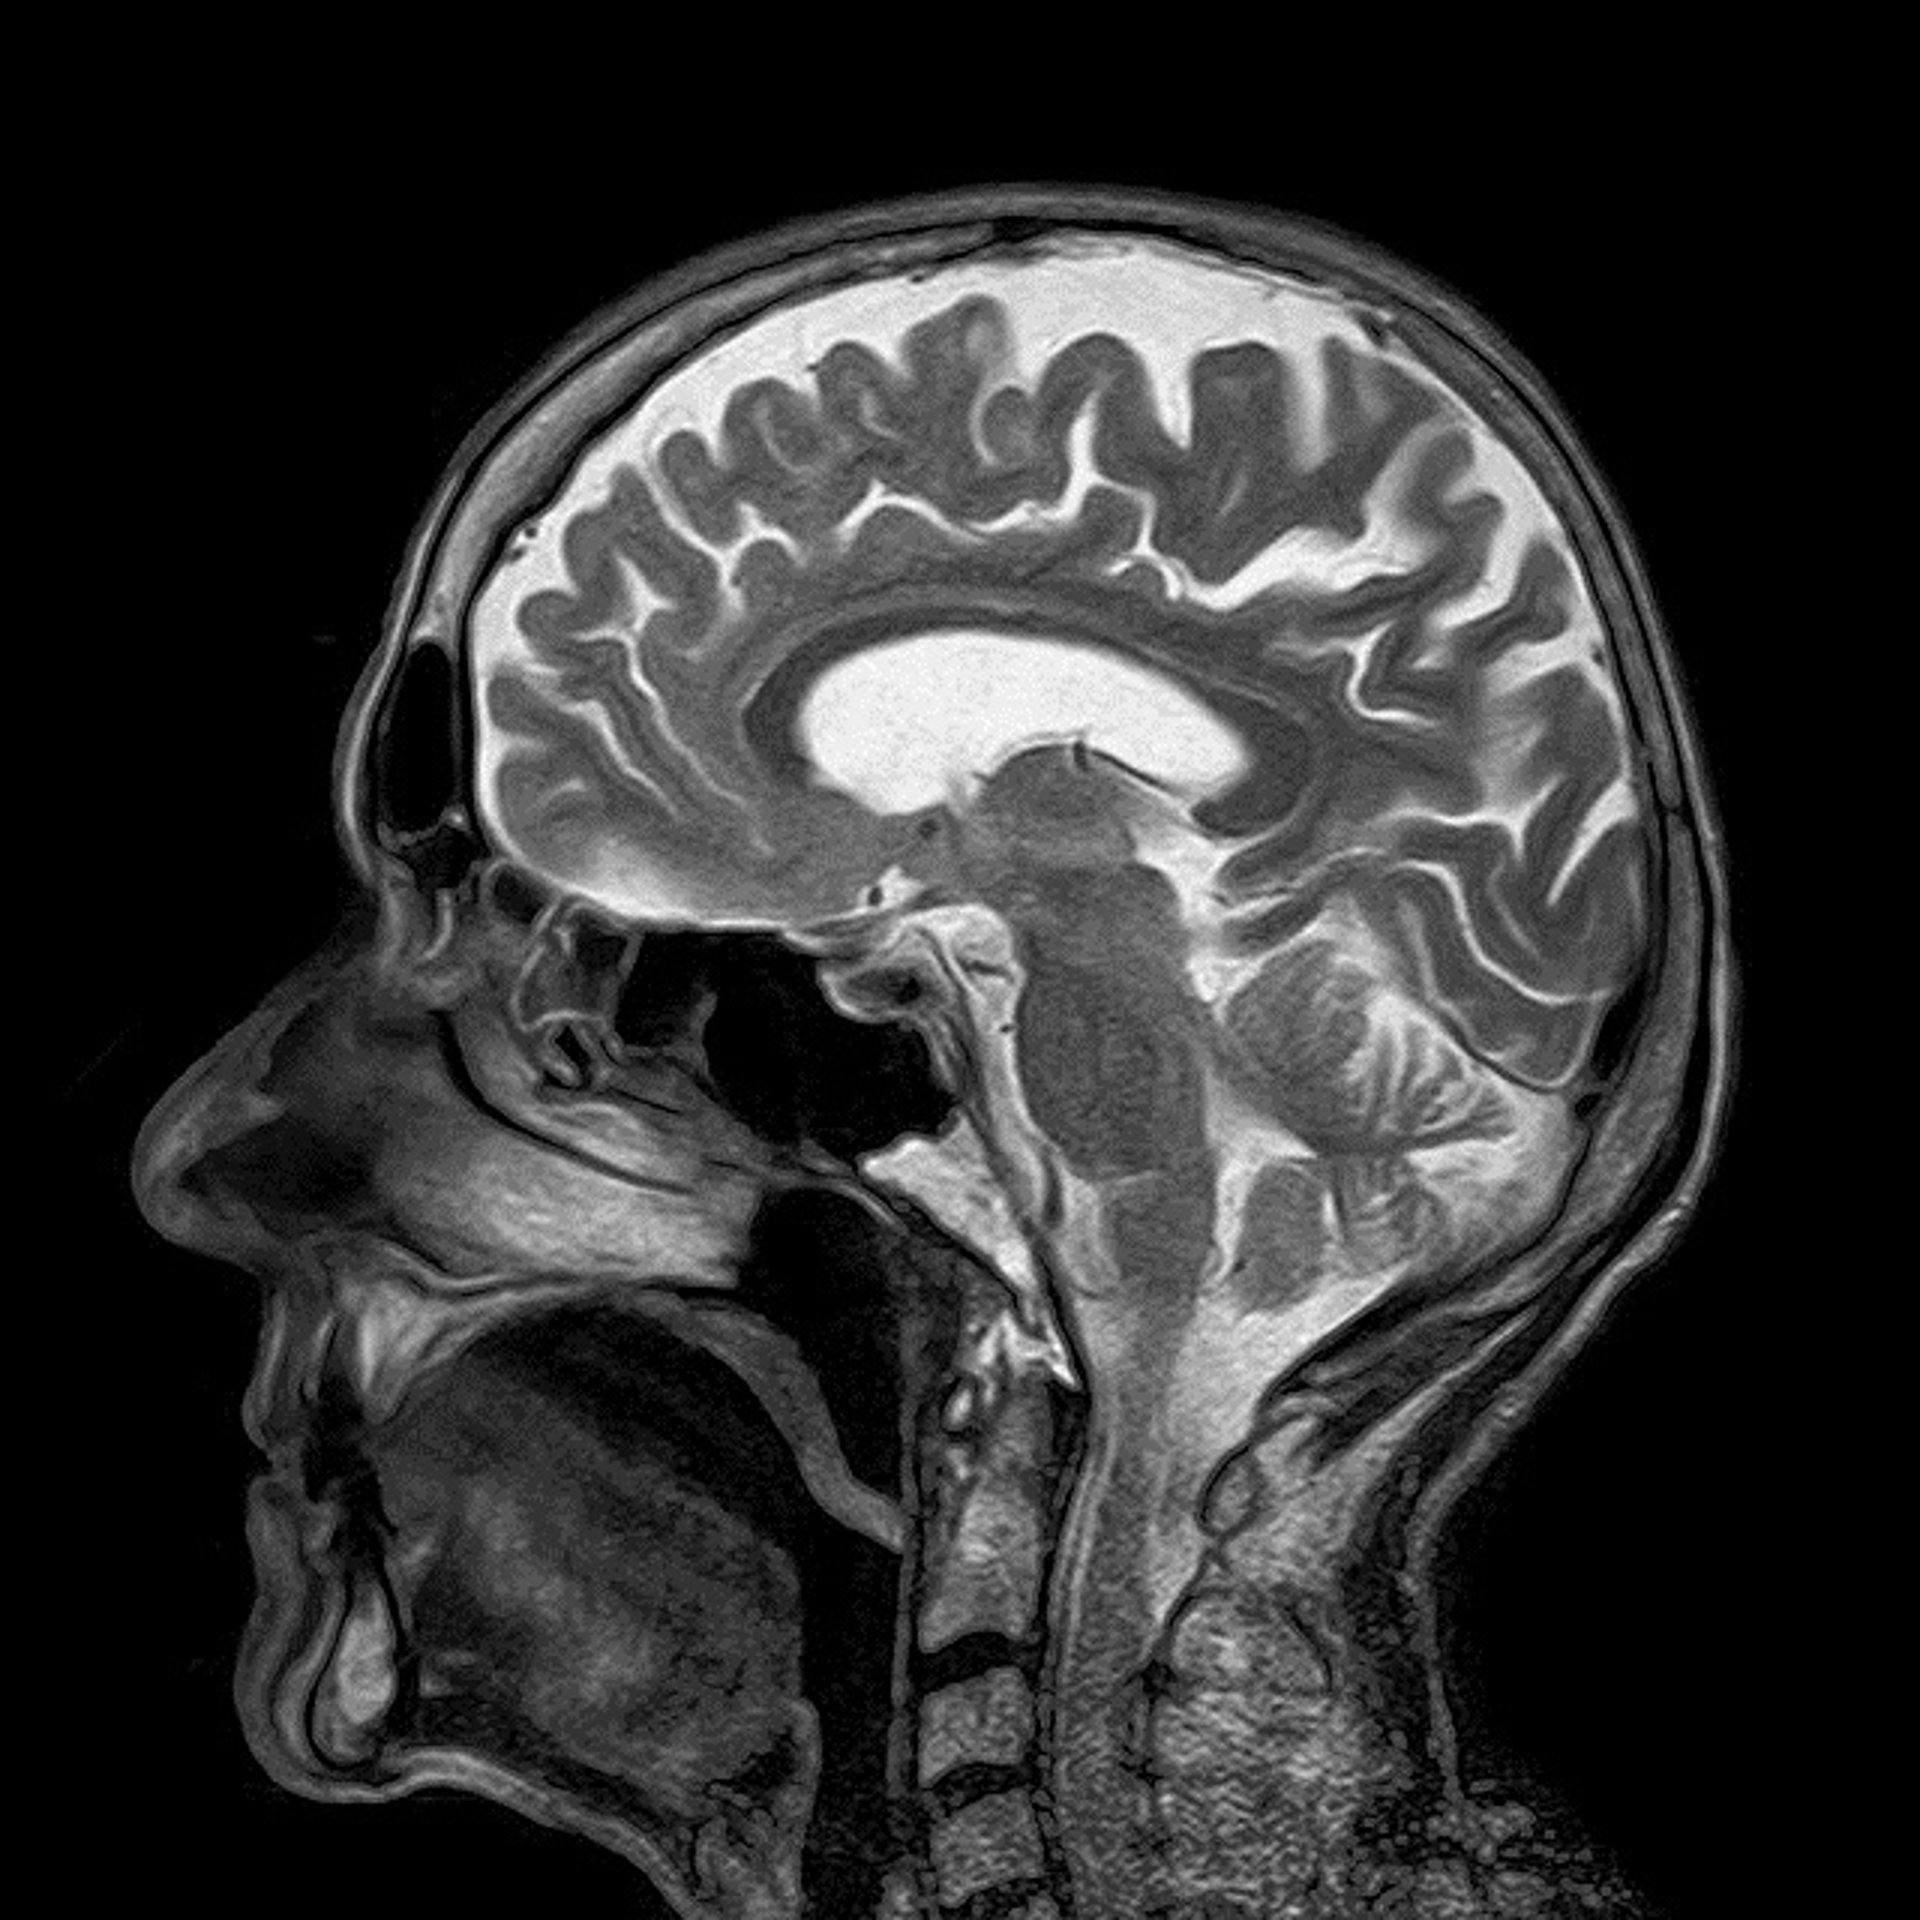

El neurobiólogo investigador del Consejo Superior de Investigaciones Científicas (CSIC), director del Cajal Blue Brain en España y codirector del Human Brain Project, Javier de Felipe Oroquieta, ha asegurado que el estudio del cerebro es el reto "más grande" al que se enfrenta el futuro de la ciencia ya que todavía queda "muchísimo por descubrir".

NUEVAS ESTRATEGIAS PARA ESTUDIAR EL CEREBRO

Ante esto, el experto ha informado de que se están desarrollando nuevas estrategias que permiten conocer cómo funcionan dichas neuronas en un circuito del cerebro humano. Para ello, los científicos están colaborando en equipos multidisciplinares, compuestos por matemáticos, ingenieros informáticos o técnicos especialistas en supercomputación, entre otros, para desarrollar tecnologías que permitan conocer de manera más rápida el funcionamiento cerebral.

"Su estudio no es sólo desde un ángulo, sino que es desde varios puntos de vida como, por ejemplo, molecular, anatómico o fisiopatológico. Por ejemplo, en mi equipo marcamos neuronas, las visualizamos con unas técnicas especiales y, posteriormente, esa estructura biológica se transforma en valores matemáticos para saber cómo están diseñadas las neuronas y los circuitos del cerebro y, así, generar ordenadores inspirados en la organización cerebral", ha comentado.